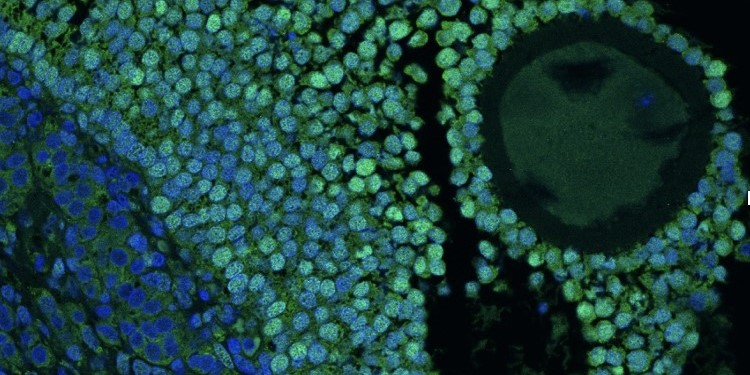

Research into the endocrinology of normal and aberrant gonadal function with an emphasis on understanding the causes, consequences and management of polycystic ovary syndrome (PCOS).

PCOS is the commonest endocrine disorder in women and is the leading cause of infrequent or absent ovulation (and therefore reduced fertility) and of hirsutism (excess body hair). It is also characterised by metabolic dysfunction (with increased risk of obesity, diabetes and cardiovascular disease), and long-term impairment of mental health.

In our long-term collaboration with Professor Aylin Hanyaloglu we have identified and characterised abnormal function of the luteinising hormone receptor (LHR) in ovarian cells from women with PCOS (PDRA, Dr Priyanka Anujan). Ongoing work is targeted at modulating the abnormally increased LHR activity to improve ovarian function in PCOS.